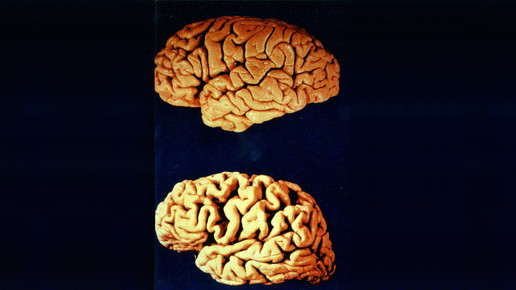

Forscher des Institut national de la santé et de la recherche médicale (Inserm), des Commissariat à l’énergie atomique et aux énergies alternatives (CEA) und der Universität Pierre & Marie Curie diagnostizierten anhand von Gehirnbiopsien bei Patienten, die an Alzheimer gestorben waren, eine deutliche Abnahme an IL-2. Daraufhin untersuchten sie das therapeutische Potential dieses Moleküls an Mäusen, die bereits Alzheimer-Symptome aufwiesen.

Die Behandlung mit IL-2 führte zu einer Ausbreitung und Aktivierung der regulatorischen T-Lymphozyten im Gehirn und damit zu einer Verringerung der Amyloid-Plaques. Die Forscher stellten fest, dass die Abnahme der Amyloid-Plaques mit einer umfassenden Gewebeveränderung einhergeht, die die Struktur und die Funktion der Synapsen verbessert.